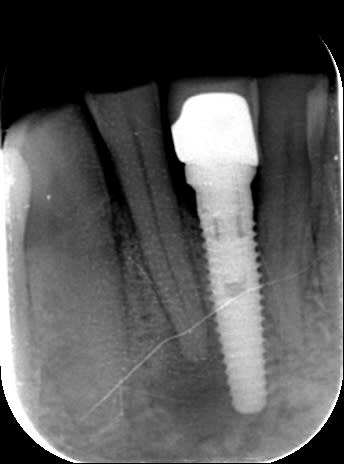

Voir la Rx ci-joint.

Abcès péri apical sur la 42, vraisemblablement suite à une nécrose. Forte usure de la face occlusale par bruxisme.

L'implant a été placé en 2006, surface TiUnite.